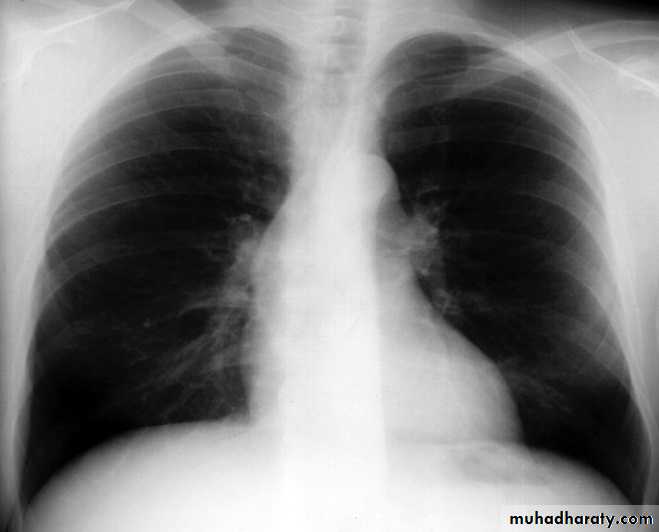

X-ray finding in PDA

Cardiac enlargement with a LV silhouetteMay be LA enlargement

Porminent ascending aorta and aorta knuckle

Plethoric lung field

Prominent PA segment

12/31/2015